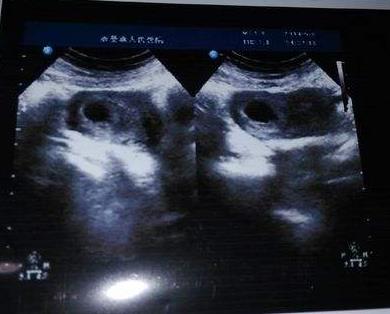

当女性知道自己怀孕后,在两个月左右会第一时间去医院检查宝宝是否发育健康。而在这个时候,我们通过B超单可以看到宝宝的孕囊形状,事实上我们可以通过宝宝的孕囊形状来判断宝宝的性别,如果孕囊形状偏向长方形,那么很可能说明你妈肚子中怀的男宝机率高一些,但是如果发现宝宝的胎囊形状属于正方形或者是椭圆形,那么这时可能孕妈怀女宝的几率比较大一些。听说这一个方法比较准,孕妈们可以拿出自己的B超单,观察一下宝宝的胎囊形状。

随着孕周期的增加,宝宝的胎心跳动也越来越强,当孕妈没听到宝宝的胎心跳动时,就会非常的激动又高兴,通常情况下我们也可以通过宝宝的胎心率来判断宝宝的性别,如果胎宝宝的胎心率维持在140左右,那么孕妈肚子中很可能怀的是男宝,而如果胎心率在150左右,那么孕妈怀女宝的几率就比较大一些,因为一般情况下,男宝要比女宝的胎心率普遍低一些。当然这种方法需要排出一些病例,或者体制方面的因素,如果孕妈比较健康,那么不妨用这个数字来判断一下宝宝的性别吧。

我们知道通过B超单上的双顶径数据,可以判断出宝宝的头围大小来,从而判断出宝宝的发育是否正常,事实上通过双顶径的数据我们也可以判断出宝宝的性别,一般情况下如果宝宝的双顶径数值减去股骨长的数值大于二或者等于20那么孕妈怀男宝的几率就会大一些,当然几种方法并没有科学依据,但是过来人的一些经验总结这几个方法还是可以参考的。